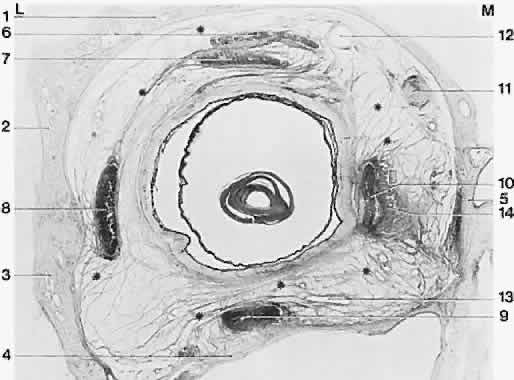

| The medial orbital walls are generally parallel; the lateral orbital walls diverge one from the other at an angle of approximately 90 degrees (Fig. 1). The orbits reach adult proportions at age 13 to 15 years, with the visual axes of the two eyes separated by 60 to 70 mm. The orbits are closer to one another in infancy, and in some children an especially narrow interocular distance leads to an appearance of the eyes being crossed, or esotropia. Growth of the nasal sinuses widens this distance. Displacement or rotation of the orbits can carry the extraocular muscles and vary the normal geometry of their action. For example, if the orbits are rotated in craniofacial disorders, the normal horizontal action of the horizontal rectus muscles takes on also a vertical action. Imaging of the bones and muscles by computed tomography (CT) or by magnetic resonance imaging (MRI) is useful to tell these variations from normal. |